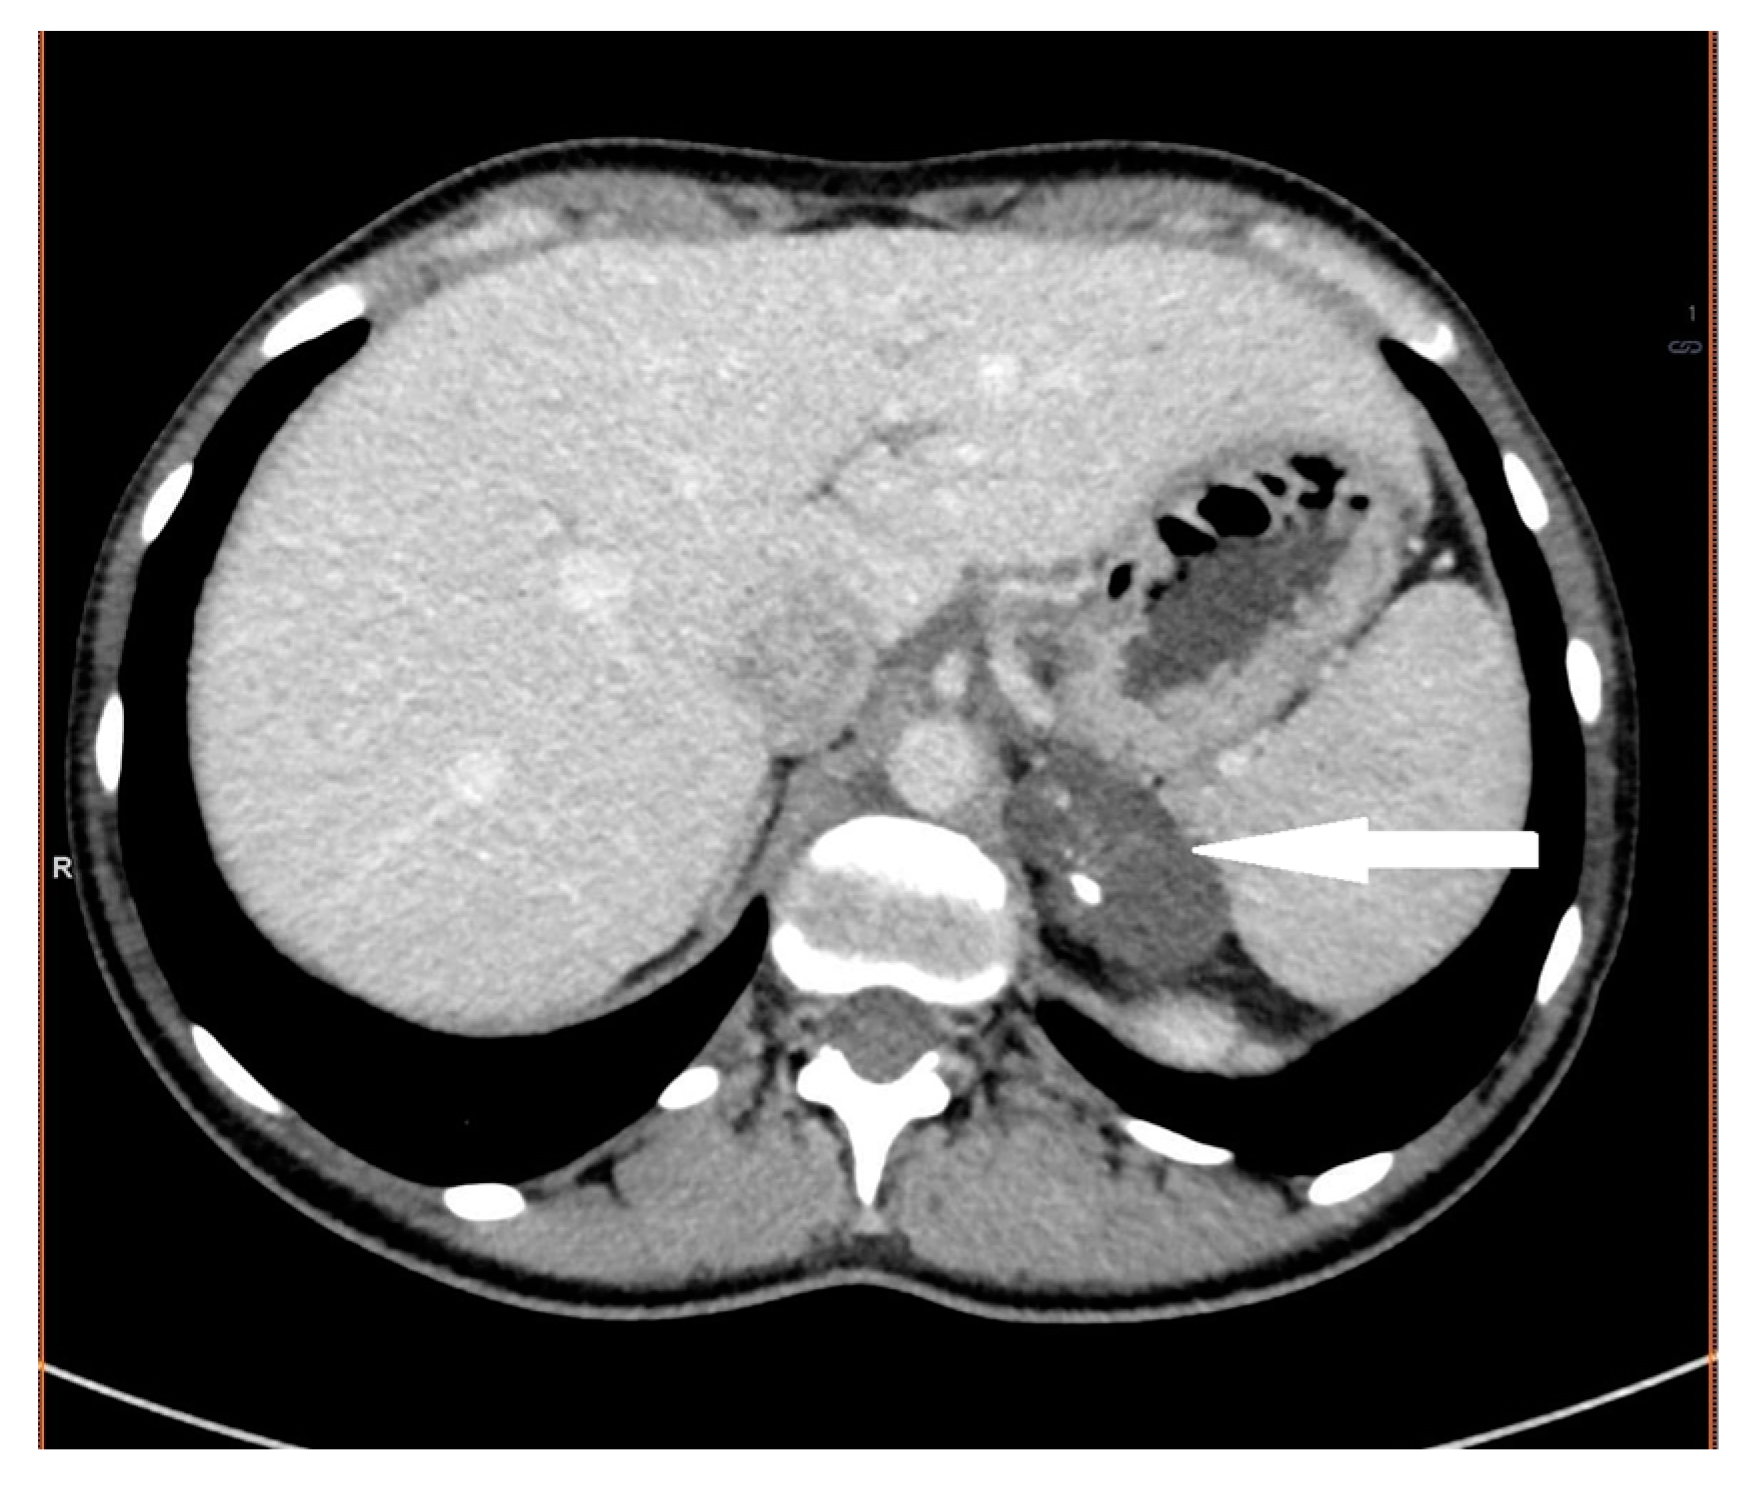

2.2. Case 2